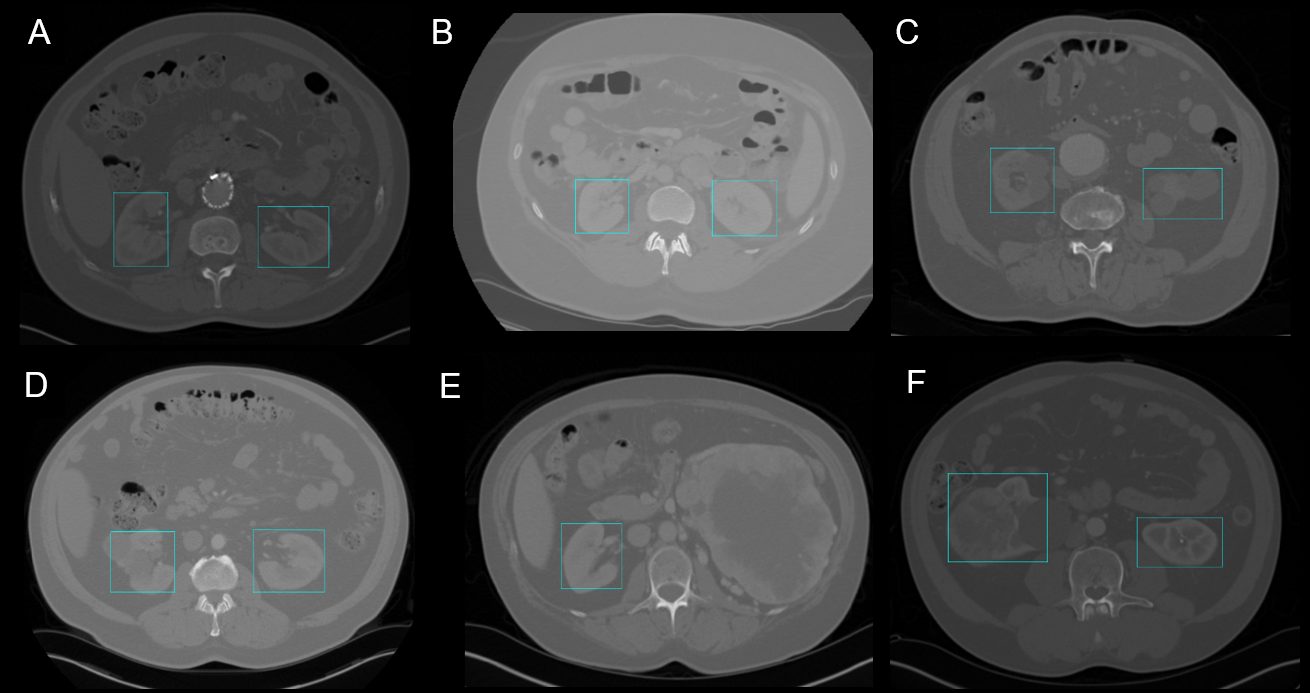

Refer to caption

Figure 1: 2D kidney detection by YOLOv3. A-B: Normal kidneys with different CT scan mean intensities. C-D: Cystic kidneys. E: Failed detection of hypertrophied kidney. F: Tumoral kidney.

YOLO showed high detection scores for the training and test sets in 2D (Dice score > 0.85) as seen in Table 1. Cystic, cancerous and healthy kidneys were recognized and located properly in CT scans largely varying in contrasts and intensities (Figure 1). The presence of artifacts caused by metal stents did not affect the performance of the model.

Difficulty with unknown ratios. The drop in performance from the training to the test set is mainly due to the failed recognition of kidney morphology unknown to the model. For instance, in Figure 1E, the kidney presented on the right has an unusual size and shape. The model only recognizes and locates the other kidney. In fact, it is known that YOLO struggles to generalize to new or unknown ratio configurations [8]. The model did well on regular looking kidneys even with tumors or cysts (Figure 1C, 1D and 1F) as long as the general morphology is preserved.

Coarseness of bounding boxes. Another factor affecting the scores is the coarseness of the boxes generated. When an object is localized, the box might not be properly framed or fitted (Figure 1F). It is reported that YOLOv3 struggles with perfectly aligning boxes with the detected objects [7].

The SSD and YOLOv3 have similar performances for 2D detection on the test set (Table LABEL:tab:scores). YOLOv3 has the speed advantage, taking only third of SSD’s time for inference. For an image of approximately 320 x 320 pixels, SSD takes 60 ms while YOLOv3 takes only 22 ms [7]. For non-time sensitive applications, SSD performs similarly to YOLOv3 (Dice: 0.851 vs 0.855 and IoU: 0.759 vs 0.747).